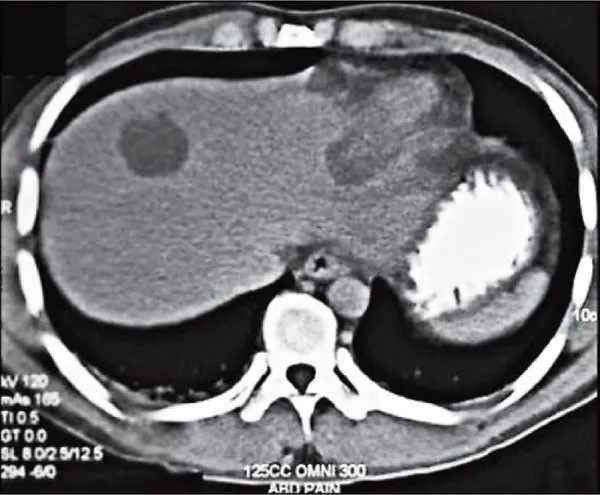

Наиболее часто встречающейся внекишечной формой амёбиаза является абсцесс печени, который в большинстве случаев формируется в правой доле печени. Клинически характеризуется высокой лихорадкой до 39-40 градусов с ознобом, повышенным потоотделением, болями в правом боку, развитием желтухи.

- УЗИ, КТ, рентгенографию органов брюшной полости;